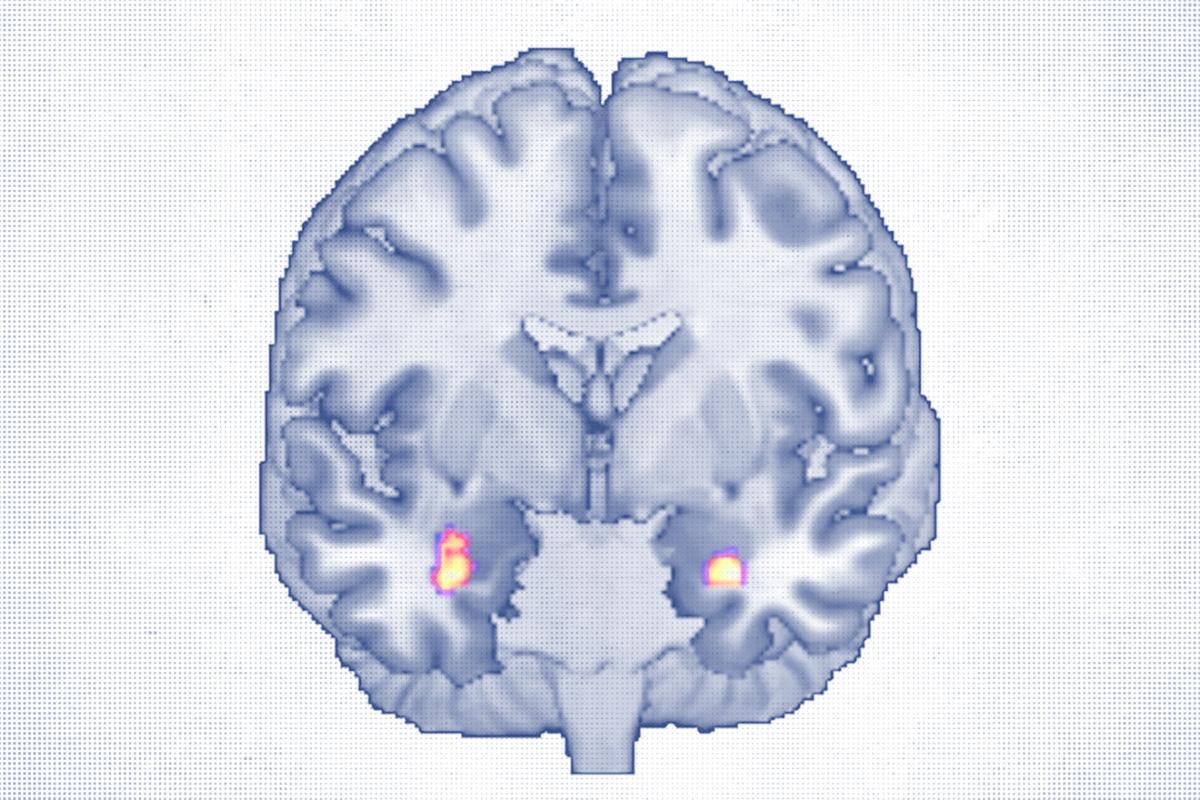

For decades, scientists have wondered whether changing the way we think could actually reshape the brain. Now, a recent study offers compelling evidence, capturing the first images suggesting that psychotherapy, through mental effort alone, may lead to real structural changes in the brain.

For people living with depression, the research points to a deeper way that therapy may help—by rebuilding the brain itself.